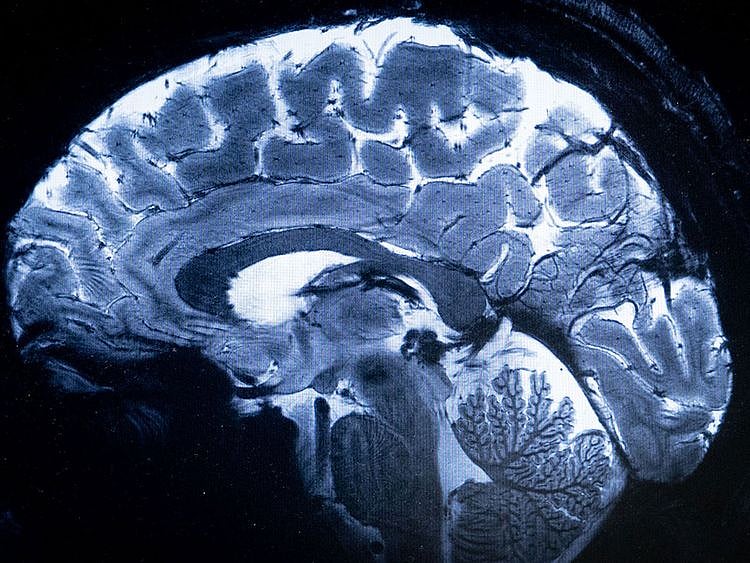

A 2012 research published in the Journal of Cognitive Neuroscience, titled “How the brain heals emotional wounds: The functional neuroanatomy of forgiveness” led by Emiliano Ricciardi, of the Department of Surgery, Medical, Molecular, and Critical Area Pathology, University of Pisa in Italy, used fMRI to examine brain activity during forgiveness.

Participants imagined scenarios involving emotional hurt, then either forgave the offender or held a grudge. This study suggests forgiveness activates areas involved in positive social interactions and managing emotions.

Another team published the results of a 2015 study, titled “Neural correlates of forgiveness: An investigation of the anterior cingulate cortex” (by SF Luo et al.). This study looked at the anterior cingulate cortex (ACC), a part of the brain involved in emotional processing.

The researchers used EEG to measure brain activity while participants decided whether to forgive someone.

What they found: Forgiveness was associated with less activity in the ACC, suggesting it may help reduce negative emotions.

In 2008, a study titled “The social neuroscience of forgiveness”, led by CE Bauman & KS McCullough, reviewed various studies on the neural correlates of forgiveness. This suggests that forgiveness may work by changing how the brain interprets and responds to social transgressions.